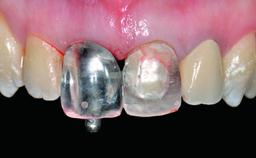

Replacement of a Failing Restored Upper Right Central Incisor, Ridge Preservation and Early Placement of an RC Bone Level Implant

A 23-year-old female, healthy and non-smoking patient had had tooth 11 temporarily restored following a trauma in adolescence. As the patient’s growth had since come to an end and the crown had fractured, she requested an implant-supported restoration of tooth 11. Moreover, the contralateral tooth 21 presented an old composite restoration at the mesial incisal edge. The periodontal tissues were healthy with periodontal probing depth values below 3 mm, but some inflammation was observed around the semi-submerged root of tooth 11.

Loading Protocol Conventional or early

Retention Cemented, with prosthesis margin < 3mm submucosal Cemented, with prosthesis margin < 3mm submucosal

Provisional Implant-Supported Prosthesis Prosthodontic margin > 3 mm apical to mucosal margin Prosthodontic margin > 3 mm apical to mucosal margin